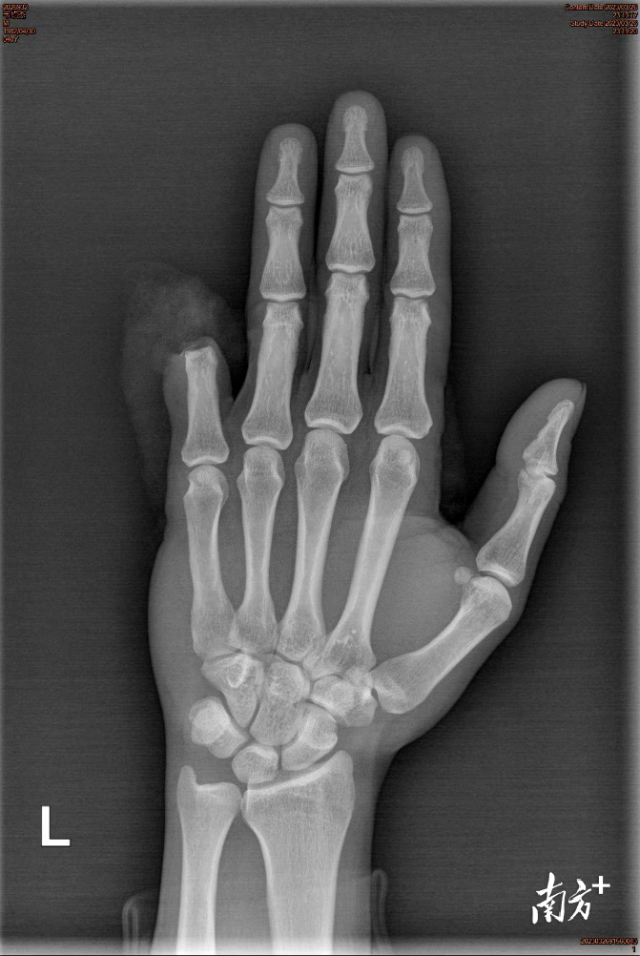

剁骨头不小心把左手小指割断,完全断离,血流不止...经历了噩梦般离指5小时,再经历术中6小时,韦先生在中山大学附属第一医院东院成功完成小指再植,手指存活良好,功能恢复也非常好,韦先生直言:“这简直就是给了我第二次工作和生活的机会”。

次日0:13,一切术前准备就绪后,骨科值班医生许银峰便在麻醉师和机械护士配合下开始手术,在术中,清创、接骨、修复手指肌腱2条,显微镜下吻合指动脉2条、指背静脉2条,指神经2条…整整持续了6个多小时,直到清晨6:45分手术顺利结束。术后患者左手小指离断部分当即由苍白变红润,再予以抗炎、抗凝、抗血管痉挛等治疗,断指存活情况良好,术后2周便顺利拆线出院。